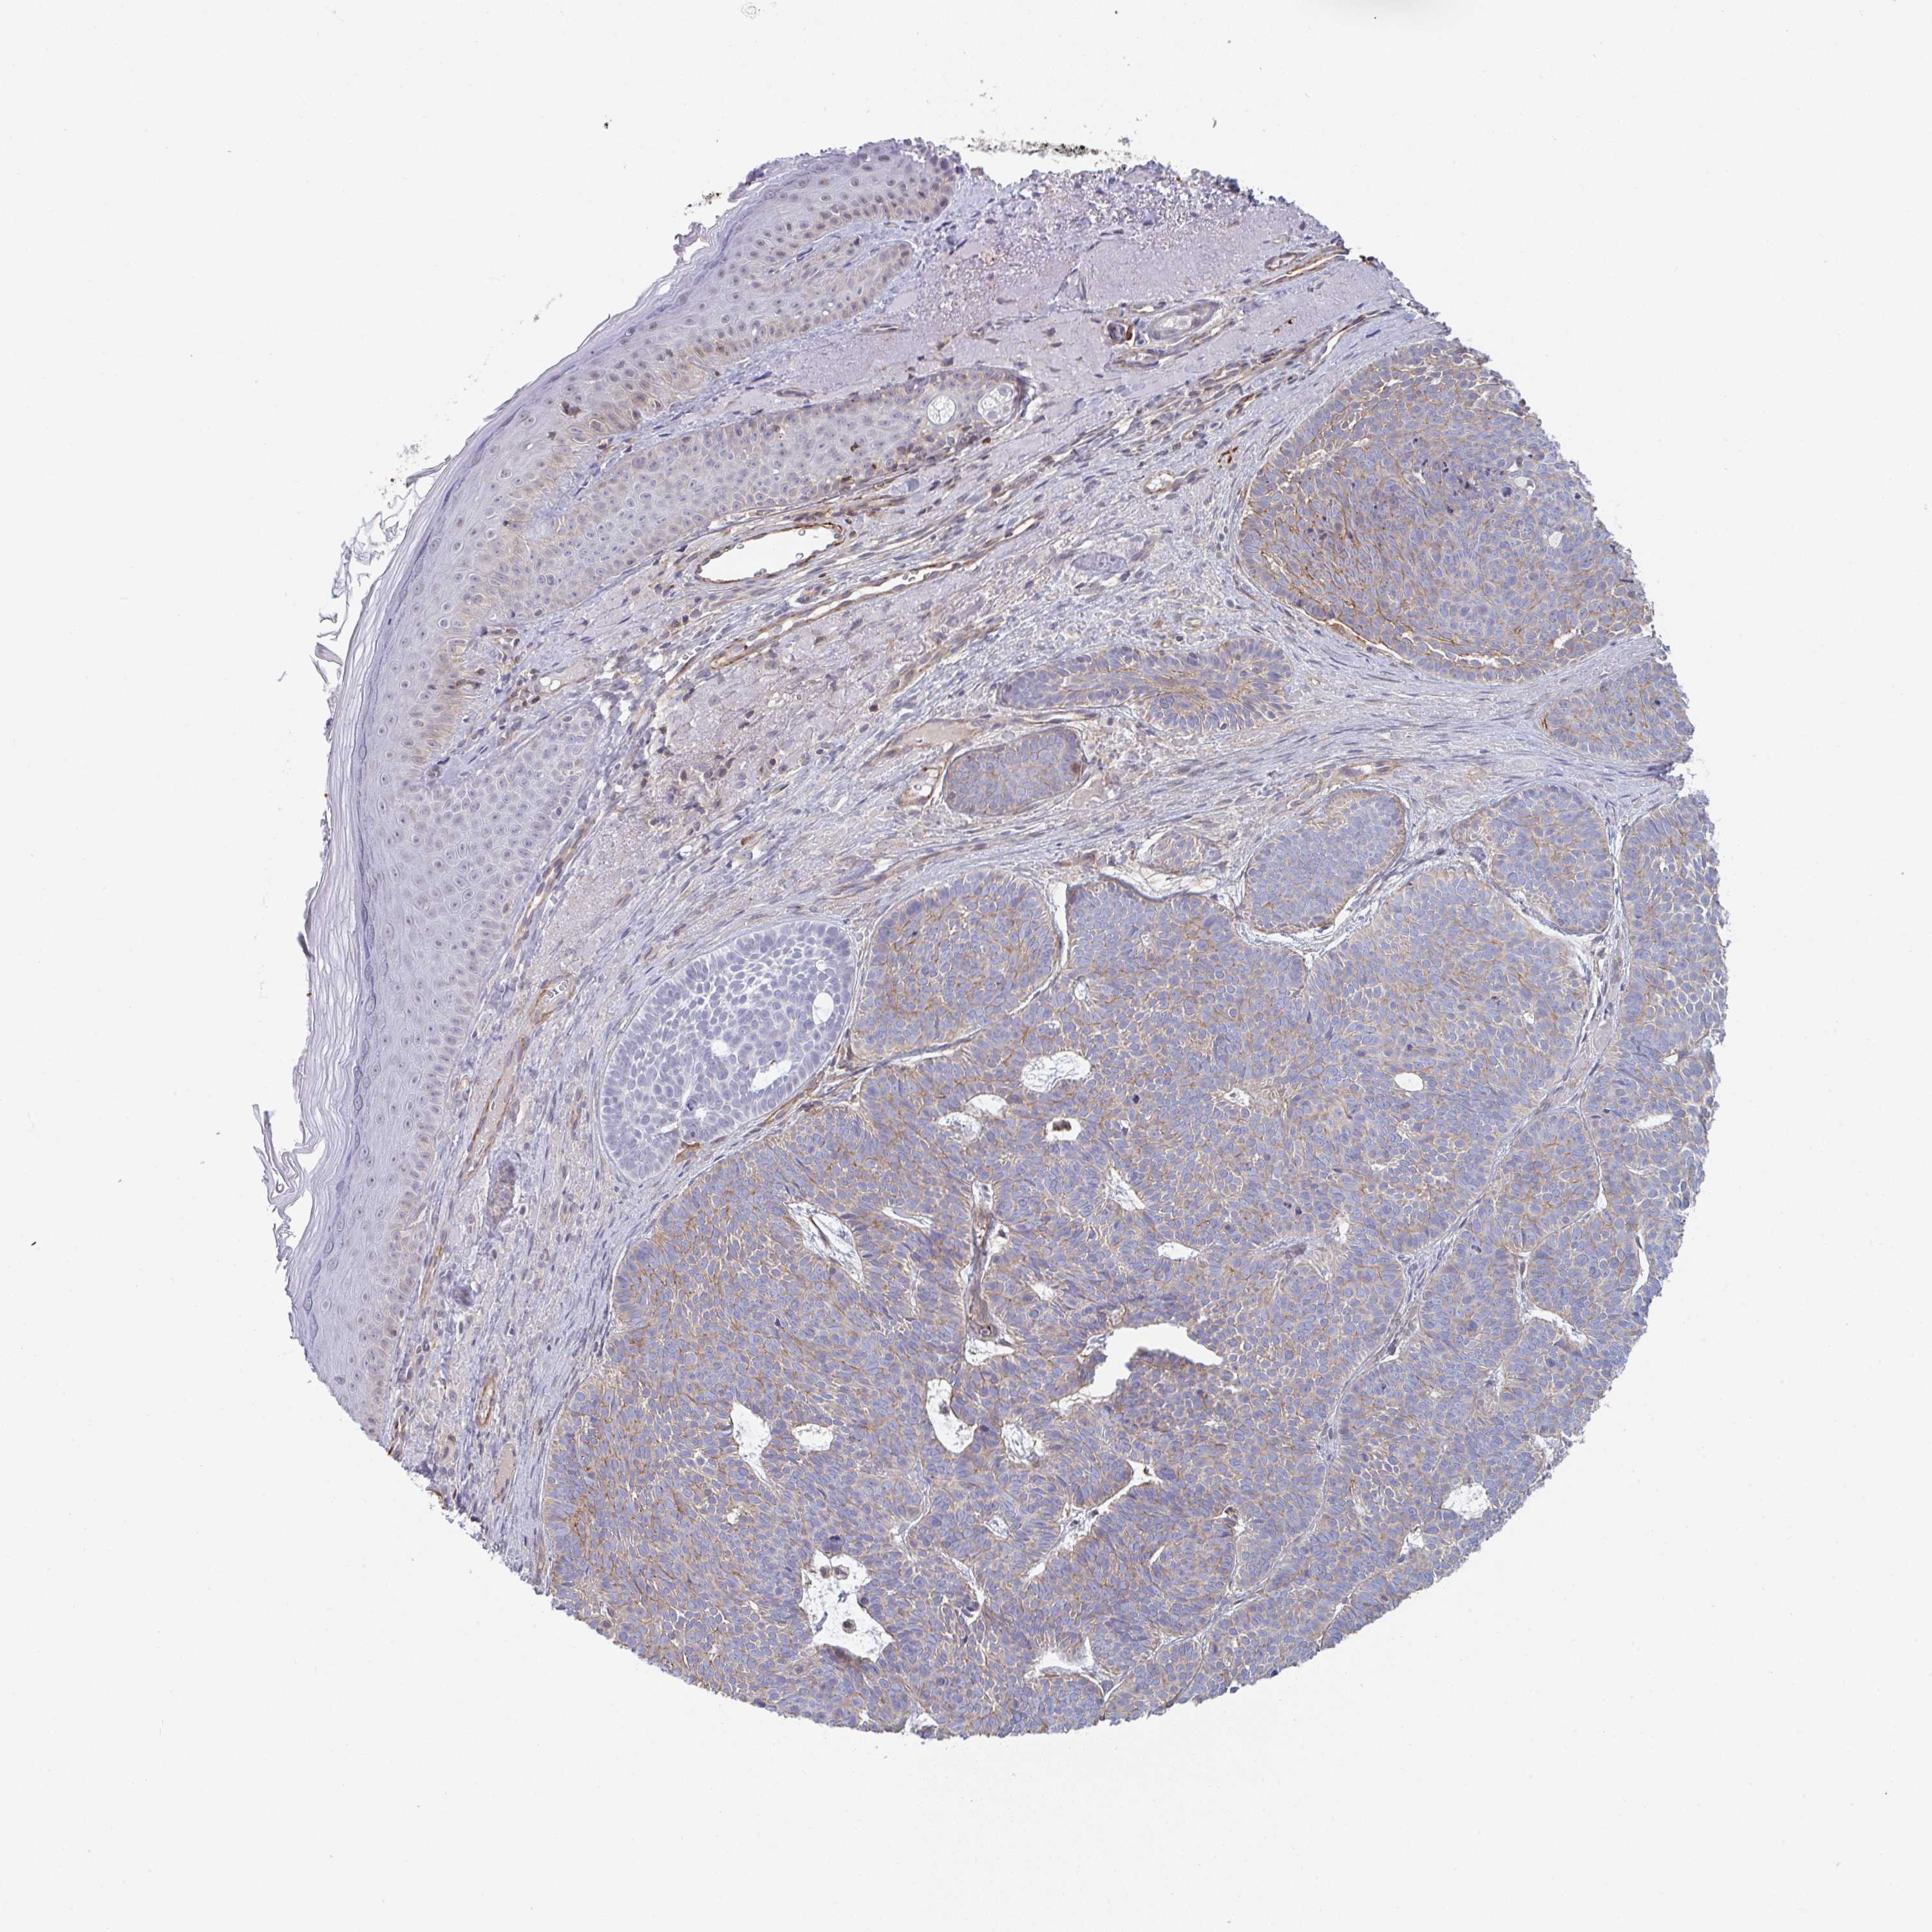

SKIN CANCER - Protein expressioni

A mouse-over function shows sample information and annotation data. Click on an image to view it in a full screen mode. Samples can be filtered based on level of antibody staining by selecting one or several of the following categories: high, medium, low and not detected. The assay and annotation is described here.

Antibody stainingi

Antibody staining in the annotated cell types in the current human tissue is reported as not detected, low, medium, or high, based on conventional immunohistochemistry profiling in selected tissues. This score is based on the combination of the staining intensity and fraction of stained cells.

Each image is clickable and will lead to virtual microscopy that enables deeper exploration of all samples and also displays staining intensity scores, fraction scores and subcellular localization as well as patient and tissue information for each sample.

Antibody HPA055314

Squamous cell carcinoma, NOS